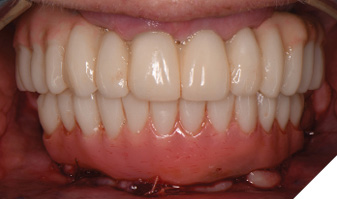

The patient returned 2 months later (due to patient scheduling delays) and the maxillary and mandibular Nexus restorations were inserted (Figs. 26A-C). Passive seating of the restorations were confirmed with the Sheffield test and radiographic confirmation. The occlusion was checked and final radiographs taken (Fig. 27).

Fig. 26A

Fig. 26B

Fig. 26C